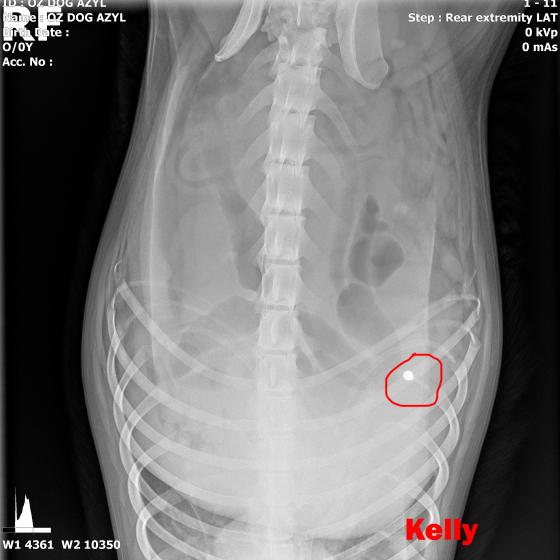

KELLY - Vzali sme ju z ranča, kde boli zvieratá v hororových podmienkach. Neudrží sa na zadných nohách. Môže to spôsobovať hneď niekoľko faktov.

Image removed.KELLY - Vzali sme ju v rámci záchrannej akcie ČSKP z ranča, kde boli zvieratá v hororových podmienkach. Jedli, čo si našli, nekontrolovane sa medzi sebou množili a vôbec nie je vylúčené, že aj na ostatných si nejaký zlomyslený človek skúšal streľbu do diaľky. Kelly je úžasná, pokorná, mierumilovná, oddaná fenka, ktorá sa tak strašne zmierila s utrpením a svojim životom, že celé dni len tíško preleží v peliešku a občas si poplačká. Užíva si každé pohladenie, ale nechce byť nenásytná lebo nevie, či sa jej aj zajtra ujde. Ťažko je ju pohladiť bez toho aby Vám pri nej slza nevytiekla. Nevieme a nechceme si ani len predstaviť akým peklom si musela už prejsť. Kelly má diagnóz hneď niekoľko. Jej primárnym problémom je hrozné krívanie, doslova hopká ako zajko. Neudrží sa na zadných nohách. Môže to spôsobovať hneď niekoľko faktov.

V ľavej packe, medzi druhým a tretím prstom mala brok (treba si to predstaviť, ako keď máte kamienok v topánke a nech stúpate akokoľvek, vždy Vás tlačí. Lenže to je len kamienok a nie cudzí predmet v živom tkanive. Tú bolesť si radšej ani nepredstavujte.) V tej istej nožičke, v oblasti zadnej strany kolena bol ďalší brok, ktorý jej tiež prekážal pri narovnaní nohy. Prvým krokom bolo odstránenie týchto dvoch brokov, ktoré pravdepodobne spôsobovali najväčšie ťažkosti. Operácia sa konala 10.5.2020, dopadla výborne, Kelly sa zotavuje.

Píšeme ale "pravdepodobne" preto, lebo Kelly má tiež problém s krížovým väzom v kolene, ktorý má známky deformácie a má tiež hypointenzitu disku (to znamená, že má na platničke medzi stavcami pruh, ktorý vyčnieva a tlačí na miechu). Veríme, že vsetci strážni anjeli pri nej budú stáť a zvládne sa zotaviť, aby si mohla užívať taký život, aký mala žiť od narodenia. My sme pri nej, zabezpečíme jej všetko potrebné! Za diagnostiku, MRI a chirurgiu máme dve faktúrky, v celkovej výške 762,05€.